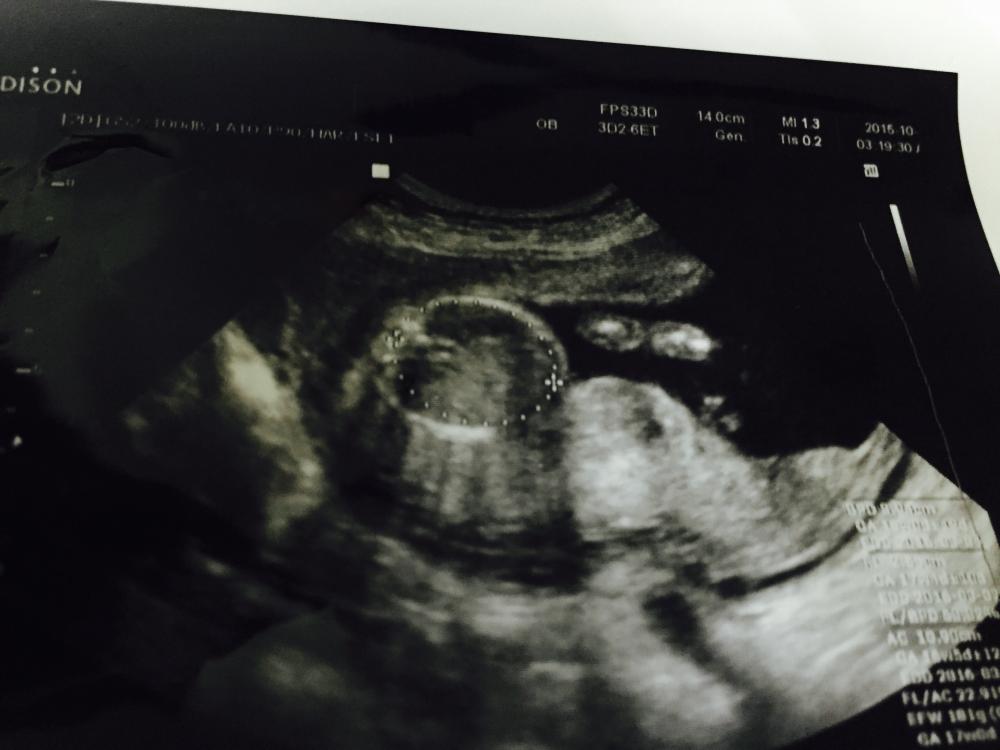

حبيبتي الله يفرحك بما تتمنى السونار في الشهر الخامس يكون واضح

واضح ولا ارجع ارسل لانها كذا وحده